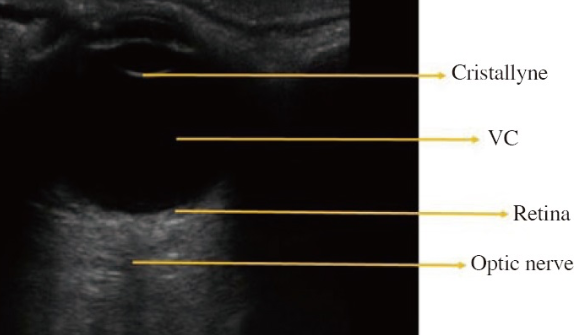

正常眼球解剖

Cristallyne:水晶体、VC(Vitreous chamber):硝子体腔、Retina:網膜、Optic nerve:視神経

Builes, Santiago Vasquez, Gonzalez, et al. Using point-of-care ultrasound in ocular emergencies: A mini review. Journal of Acute Disease 9:p 190-193, September 2020. より引用